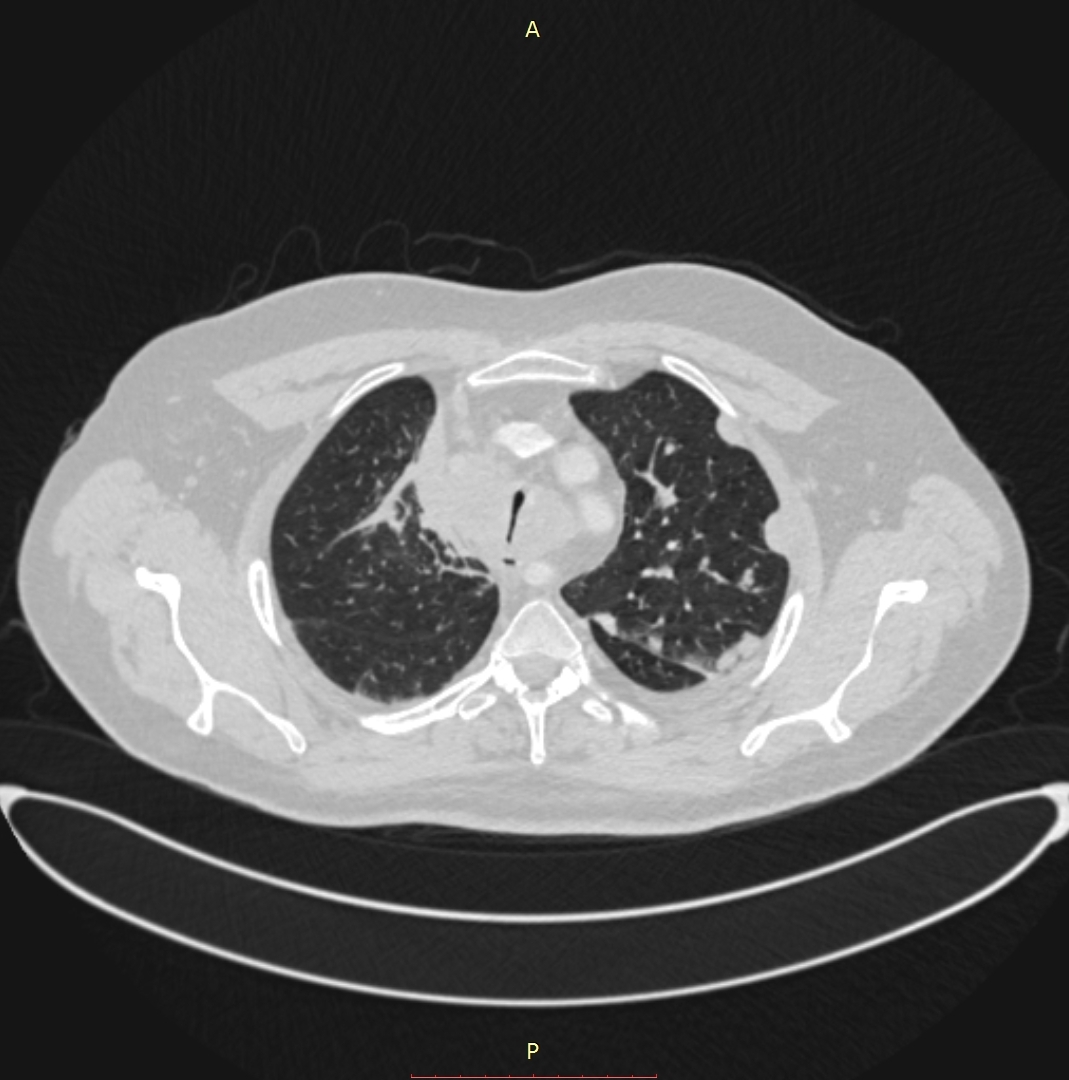

პაციენტი, 41 წლის მამაკაცი, 2015 წლის ოქტომბერში დაესვა მარჯვენა ფილტვის ბრტყელუჯრედოვანი გაურქოვანებელი კარცინომის დიაგნოზი. მიუხედავად ქიმიოთერაპიისა და რადიაციული თერაპიისა, პაციენტის კლინიკო-ლაბორატორიული და რადიოლოგიური მონაცემები გაუარესდა. გაუჩნდა სტრიდორული სუნთქვა, მოხრჩობის შეგძნება, ძლიერი ქოშინი მოსვენებულ მდგომარეობაშიც. 2016 წლის 1 სექტემბრის კტ კვლევით ინახა ტრაქეის გარშემო მუფტასავით შემოხვეული გადიდებული ლიმფური კვანძების კონგლომერატი, რომლებიც კრიტიკულად ავიწროებენ ტრაქეის სანათურს. ქირურგების შეფასებით ტრაქეოსტომიული მილის ჩადგმა იყო შეუძლებელი. გადაწყდა სასიცოცხლო ჩვენებით ტრაქეის სტენტირება. პაციენტის დაინტუბირების შეუძლებლობის გამო მანიპულაცია ჩატარდა ადგილობრივი გაუტკივარებით. მანიპულაციამდე პაციენტს ჩაუტარდა სუნთქვითი ვარჯიში, რის შედეგადაც მან შესძლო სუნთქვის შეკავება 10 წმ-მდე ინდეფლატორით სტენტის გაშლის დროს. შედეგი იყო მყისიერი. პაციენტს გაუქრა სტრიდორი, სატურაცია აიწია 96-97%-მდე.